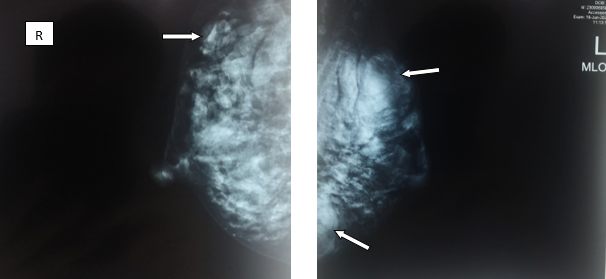

X-quang tuyến vú: nhiều khối đồng đậm độ hai vú, bờ đa cung, không có vi vôi hóa

Hình 3: Chụp X-quang tuyến vú hai bên thấy các khối đồng đậm độ ở hai bên tuyến vú (mũi tên)